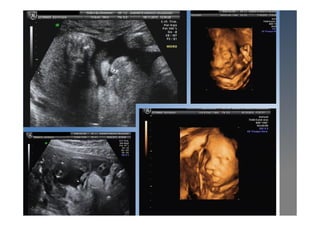

CIV

• Es la cardiopatía congénita más frecuente al

nacimiento.

• Dx: se debe asegurar con el doppler

• Tipos:

 Musculares (gen. cierran 1º año de vida

salvo muy grandes)

 Membranosas

Corazón normal